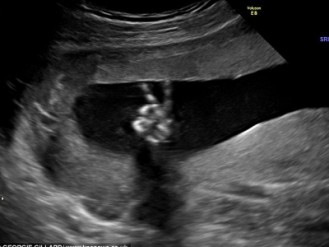

അഞ്ചാം മാസത്തില് സ്കാന് ചെയ്തു കഴിഞ്ഞ്, റിപ്പോര്ട്ട് കണ്ട് സോണോഗ്രാഫര് ഉള്പ്പെടെ എല്ലാവരും ആശ്ചര്യപ്പെട്ടു പോയി. ഗര്ഭത്തിലെ കുഞ്ഞ് തന്റെ കുഞ്ഞു വിരലുകള് ഉയര്ത്തി വിജയചിഹ്നമായ \'വി\' എന്നു കാണിക്കുന്ന സ്കാന് ചിത്രം കണ്ടപ്പോള് \'ഒന്നിനെകുറിച്ചും ആശങ്കപ്പെടേണ്ട എല്ലാം ഭംഗിയാവും\' എന്ന് ആ കുഞ്ഞ് അവരെ ആശ്വസിപ്പിക്കുന്നതു പോലെ അവര്ക്കു തോന്നി.

ആ കുഞ്ഞ് ആണ്കുഞ്ഞാണെങ്കില്, വിജയ ചിഹ്നം ഉയര്ത്തികാണിച്ചതു കൊണ്ട് അവന് വിന്സ്റ്റണ് എന്നു പേരിടണമെന്നു തീരുമാനിച്ചിരിക്കുകയാണ് അവര്. തത്കാലം ഇപ്പോള് കുഞ്ഞിനെ സമാധാനക്കുട്ടി അഥവാ പീസ് ബേബി എന്ന ഓമനപ്പേരിട്ടാണ് വിളിക്കുന്നത്.